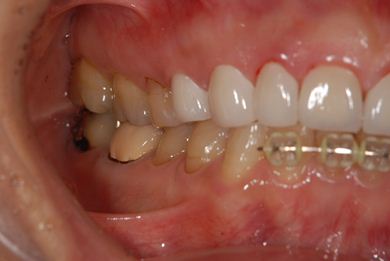

部分矯正治療+セラミック治療

| 性別/年齢 | 女性 / 54歳 | ||||||||||||||||||||||||||||||||

| 主訴 | 下の前歯のゆがみが気になり、相談。 | ||||||||||||||||||||||||||||||||

| 治療方針 | 上顎前歯の叢生を部分矯正にて審美的回復を行い、上顎前歯はラミネートベニアにて審美的回復を行う。 | ||||||||||||||||||||||||||||||||

| 治療内容 | 唇側部分矯正(ホワイト)、オールセラミックラミネートベニア8本 | ||||||||||||||||||||||||||||||||